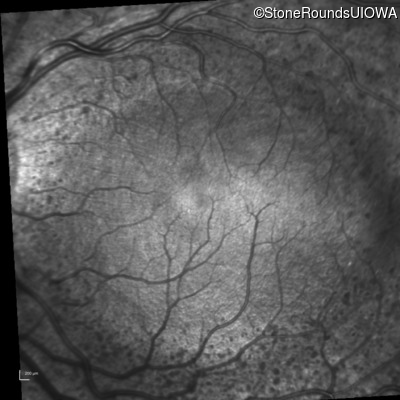

Infrared Fundus Photograph - Right - 20/50

Exemplar

Infrared Fundus Photograph - Left - 20/32